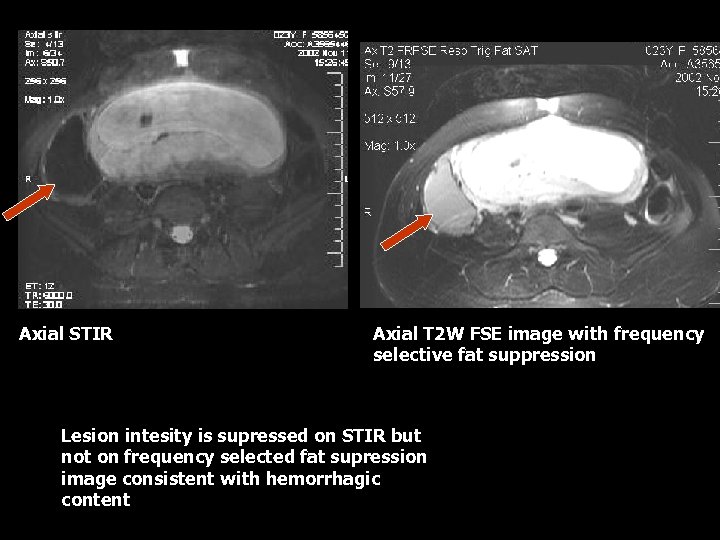

Axial STIR Axial T 2 W FSE image with frequency selective fat suppression Lesion intesity is supressed on STIR but not on frequency selected fat supression image consistent with hemorrhagic content

Hemorrhagic Cyst • Hemorrhagic cysts have typical appearance of blood products on T 1 W and T 2 W images(7). • T 1 weighted images will demonstrate low intensity due to subacute blood(7). • T 2 weighted images will demonstrate high signal(7). • Fat suppressed images • As the cyst ages, a hemosiderin rim will have low signal intensity on all sequesnces(7).